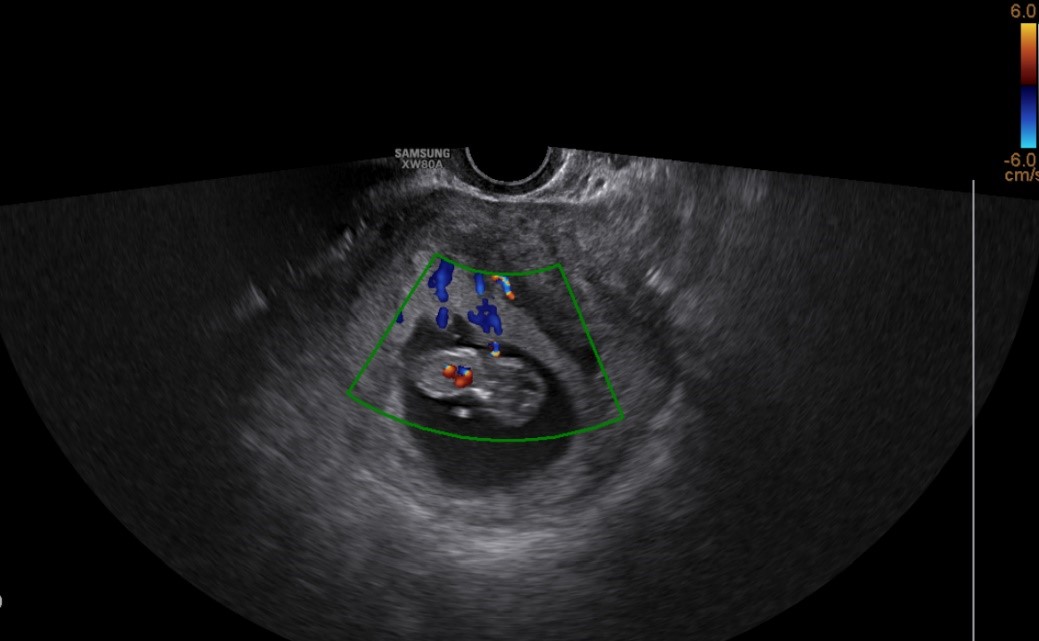

试管婴儿的B超图片

该夫妇虽然获取了精子,可是数量稀少、畸形率极高,这要求胚胎学家不仅要有高超的显微操作技术,更需具备解冻精子的成熟技巧以及甄别优质精子潜能的“火眼金睛”。我院生殖医学中心副主任徐志鹏带领本中心胚胎实验室团队,凭借高超的单精子显微注射(ICSI)技术,从有限的资源中精准筛选出形态最佳的精子顺利完成受精,置于时差培养系统中使得胚胎得以稳步发育。最终,结合人工智能筛选出最具发育潜能的2枚分裂期胚胎移植回母体子宫并且将其余具备发育潜能的囊胚冷冻保存,为这个家庭留下了珍贵的“新生希望”。